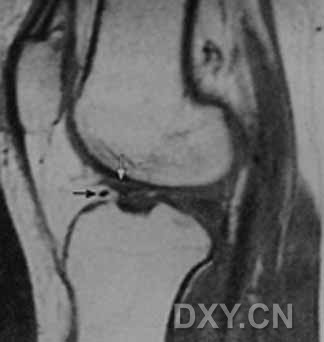

| Ⅱ级,见黑箭头